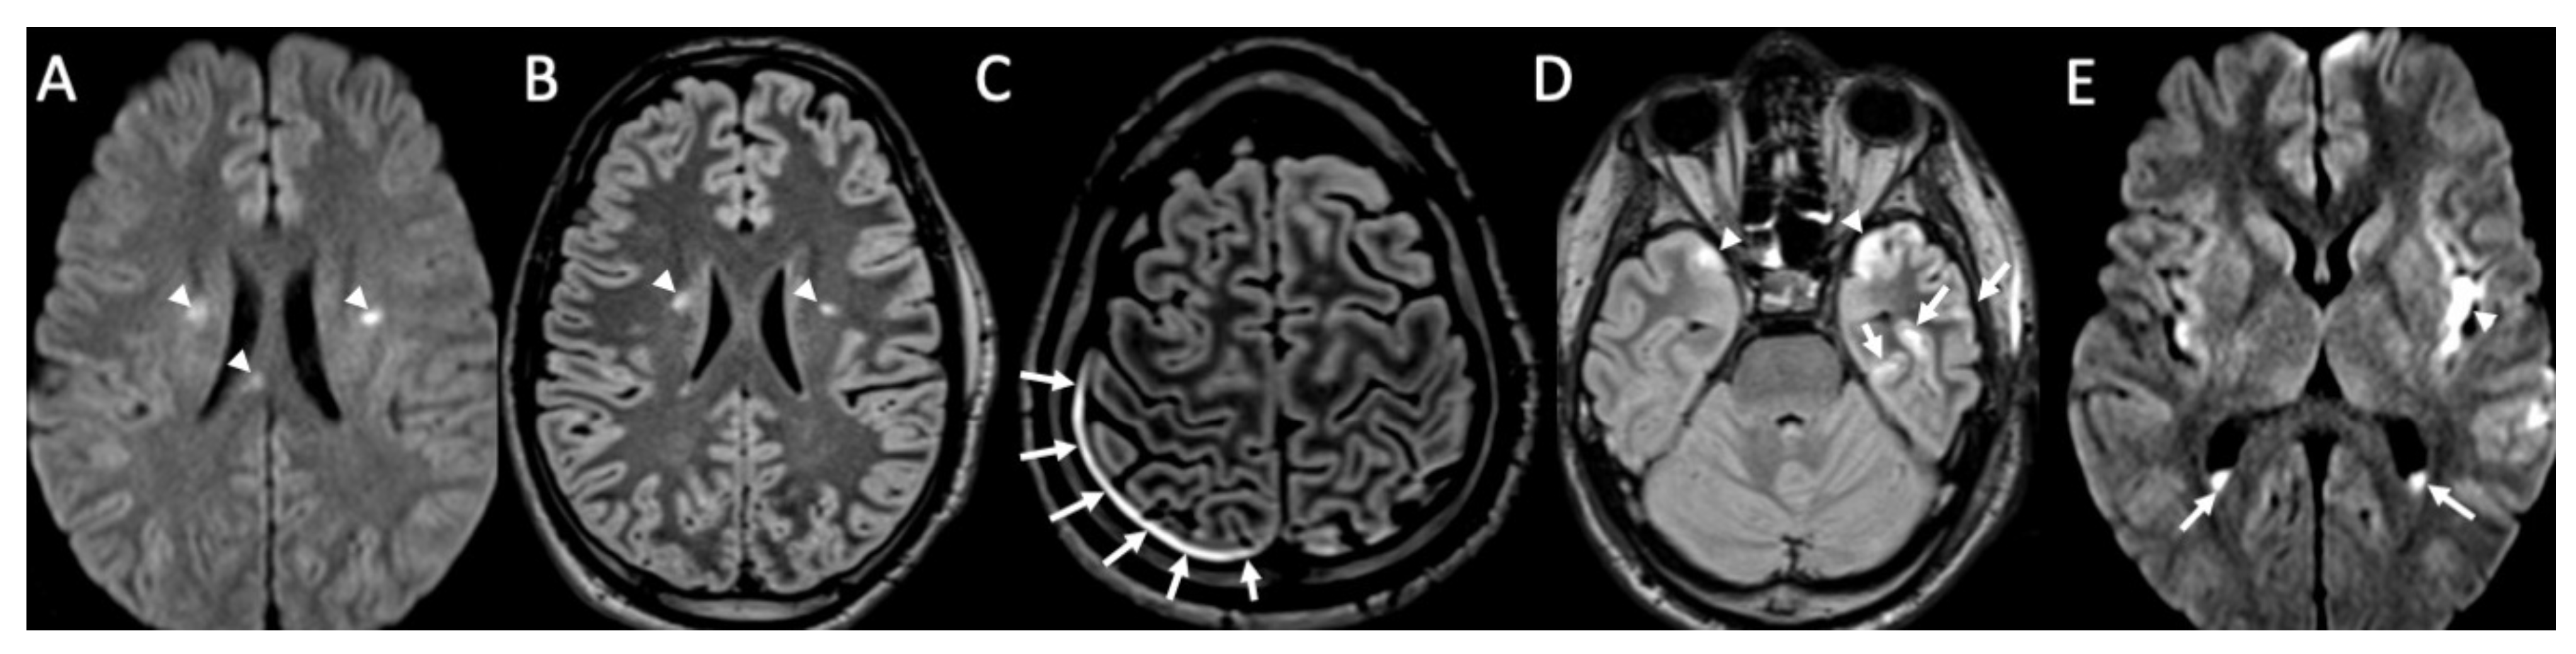

| Piogenic Meningitis | • Cerebrospinal fluid hyperintensity in T1 and FLAIR • Restricted diffusion of the subarachnoid spaces • Meningeal enhancement on T1 and FLAIR |

| Tuberculosis | • Leptomeningeal enhancement in the basal cisterns • Hydrocephalus very common • Infarcts in the basal ganglia due to vasculitis • Possible concomitant tuberculomas or miliary tuberculosis |

2. Piogenic Meningitis

3. Tuberculous Meningitis/Meningoencephalitis